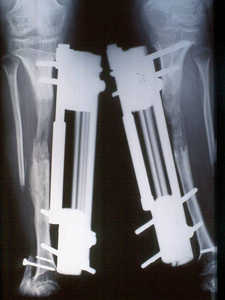

Existe una segunda técnica de crecimiento, esta vez para adultos, que cada vez es más solicitada. Se trata de la Elongación Ósea. Este consiste en producir una micro fractura controlada en el hueso, el cual, por sus mecanismos normales de sanación, producirá nuevo hueso para reparar la fractura. Se procede luego a separar las partes fracturadas, obligando al hueso a crear nuevo tejido en el espacio vacío, alargándolo. Con esta técnica se pueden crecer hasta cerca de 10 centímetros dependiendo de las proporciones del cuerpo.. Las microfracturas son hechas en las piernas. Es sin dudas un tratamiento muy sacrificado.